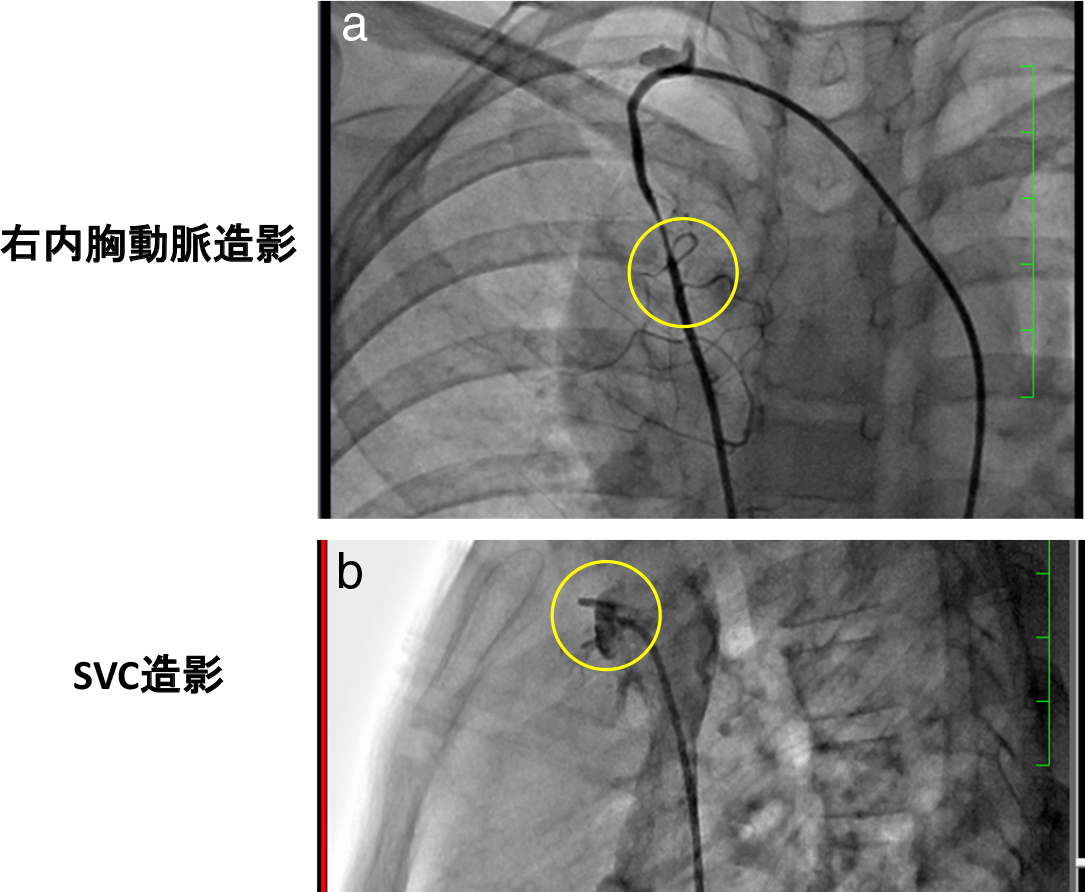

血管造影(8歳時)

右内胸動脈から分岐する血管が腫瘤に流入しており(a),SVCに還流する異常血管を認める(b).

現病歴:8歳時に咳と発熱を主訴に近医を受診,胸部X線検査で右下肺野の浸潤影と縦隔側の腫瘤影を認めた(Fig. 1a).肺炎の診断で内服治療を行い,症状は改善したが,再検の胸部X線検査でも腫瘤影は残存していた(Fig. 1b).腫瘤性病変疑いで前医を紹介受診し,胸部computed tomography(以下CT)で前縦隔に腫瘤を認め,精査加療目的で当院を紹介入院した.血液検査では,異常は認めなかった.造影CTでは,前縦隔右側から心臓右縁にかけて44 × 32 mmの腫瘤を認め,石灰化はなく造影効果もなかった.胸腺に広く接しているが,境界は明瞭であった(Fig. 2a).腫瘤内に上大静脈(superior vena cava;以下SVC)に連続する拡張した異常血管構造を多数認めた(Fig. 2a)が,明らかな流入動脈は同定出来なかった.造影magnetic resonance imaging(以下MRI)ではT1強調像で筋と同程度の中間信号,T2強調像で低~高信号が混在していた(Fig. 2b).Dynamic studyではslow-persistent patternの増強効果(早期相で軽度の信号上昇を認め,遅延相にかけて漸増性に信号上昇する.良性腫瘍で主にみられるパターン.)を呈し,内部に拡張した血管構造があり,SVCと連続していた.T1強調像のopposed-phase(脂肪と脂肪以外の成分の信号が打ち消し合う相.少量の脂肪成分の検出に用いられる.)で脂肪成分を認めなかった.悪性疾患の否定目的で施行したpositron-emission tomography(以下PET-CT)では,FluoroDeoxyGlucoseの異常集積を認めなかった.摘出術を想定した場合,流出入血管を同定・把握しておく事は不可欠であり,診断的意味を含めて血管造影を行った.血管造影では,右内胸動脈から分岐する血管が腫瘤に流入しており(Fig. 3a),SVCに還流する異常血管を認める(Fig. 3b)が,逆行性造影では腫瘤内部は造影されなかった.以上の結果から,胸腺腫や奇形腫としては非典型的であり,血管腫などの間葉系良性腫瘍や肺葉外肺分画症を鑑別に挙げ,無症状であることから,経過観察の方針とした.